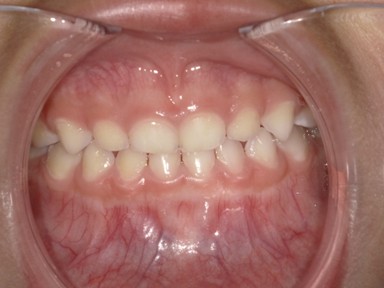

| 主訴 | 受け口を治したい。 |

| 治療内容 | ・使用装置:- マイオブレース(J1, J2) ・ワイヤー矯正および拡大装置等:未使用 ・抜歯:なし |

| 治療期間 | 2017年9月~2018年8月(現在も定期的に保険にて観察中) |

| 想定されたリスク | マイオブレースの装着状況によっては結果が得られず、その他の矯正器具を使用する可能性がありました。 |

乳歯の反対咬合は様子を見ましょうと言われることが多いですが、上顎の前方発育を阻害する大きな要因となりますので、早期の介入をおすすめしています。反対咬合は1年で改善し、現在は定期健診で様子を見ています。装置を付けることなく、良好に生え変わりが進んでいます。